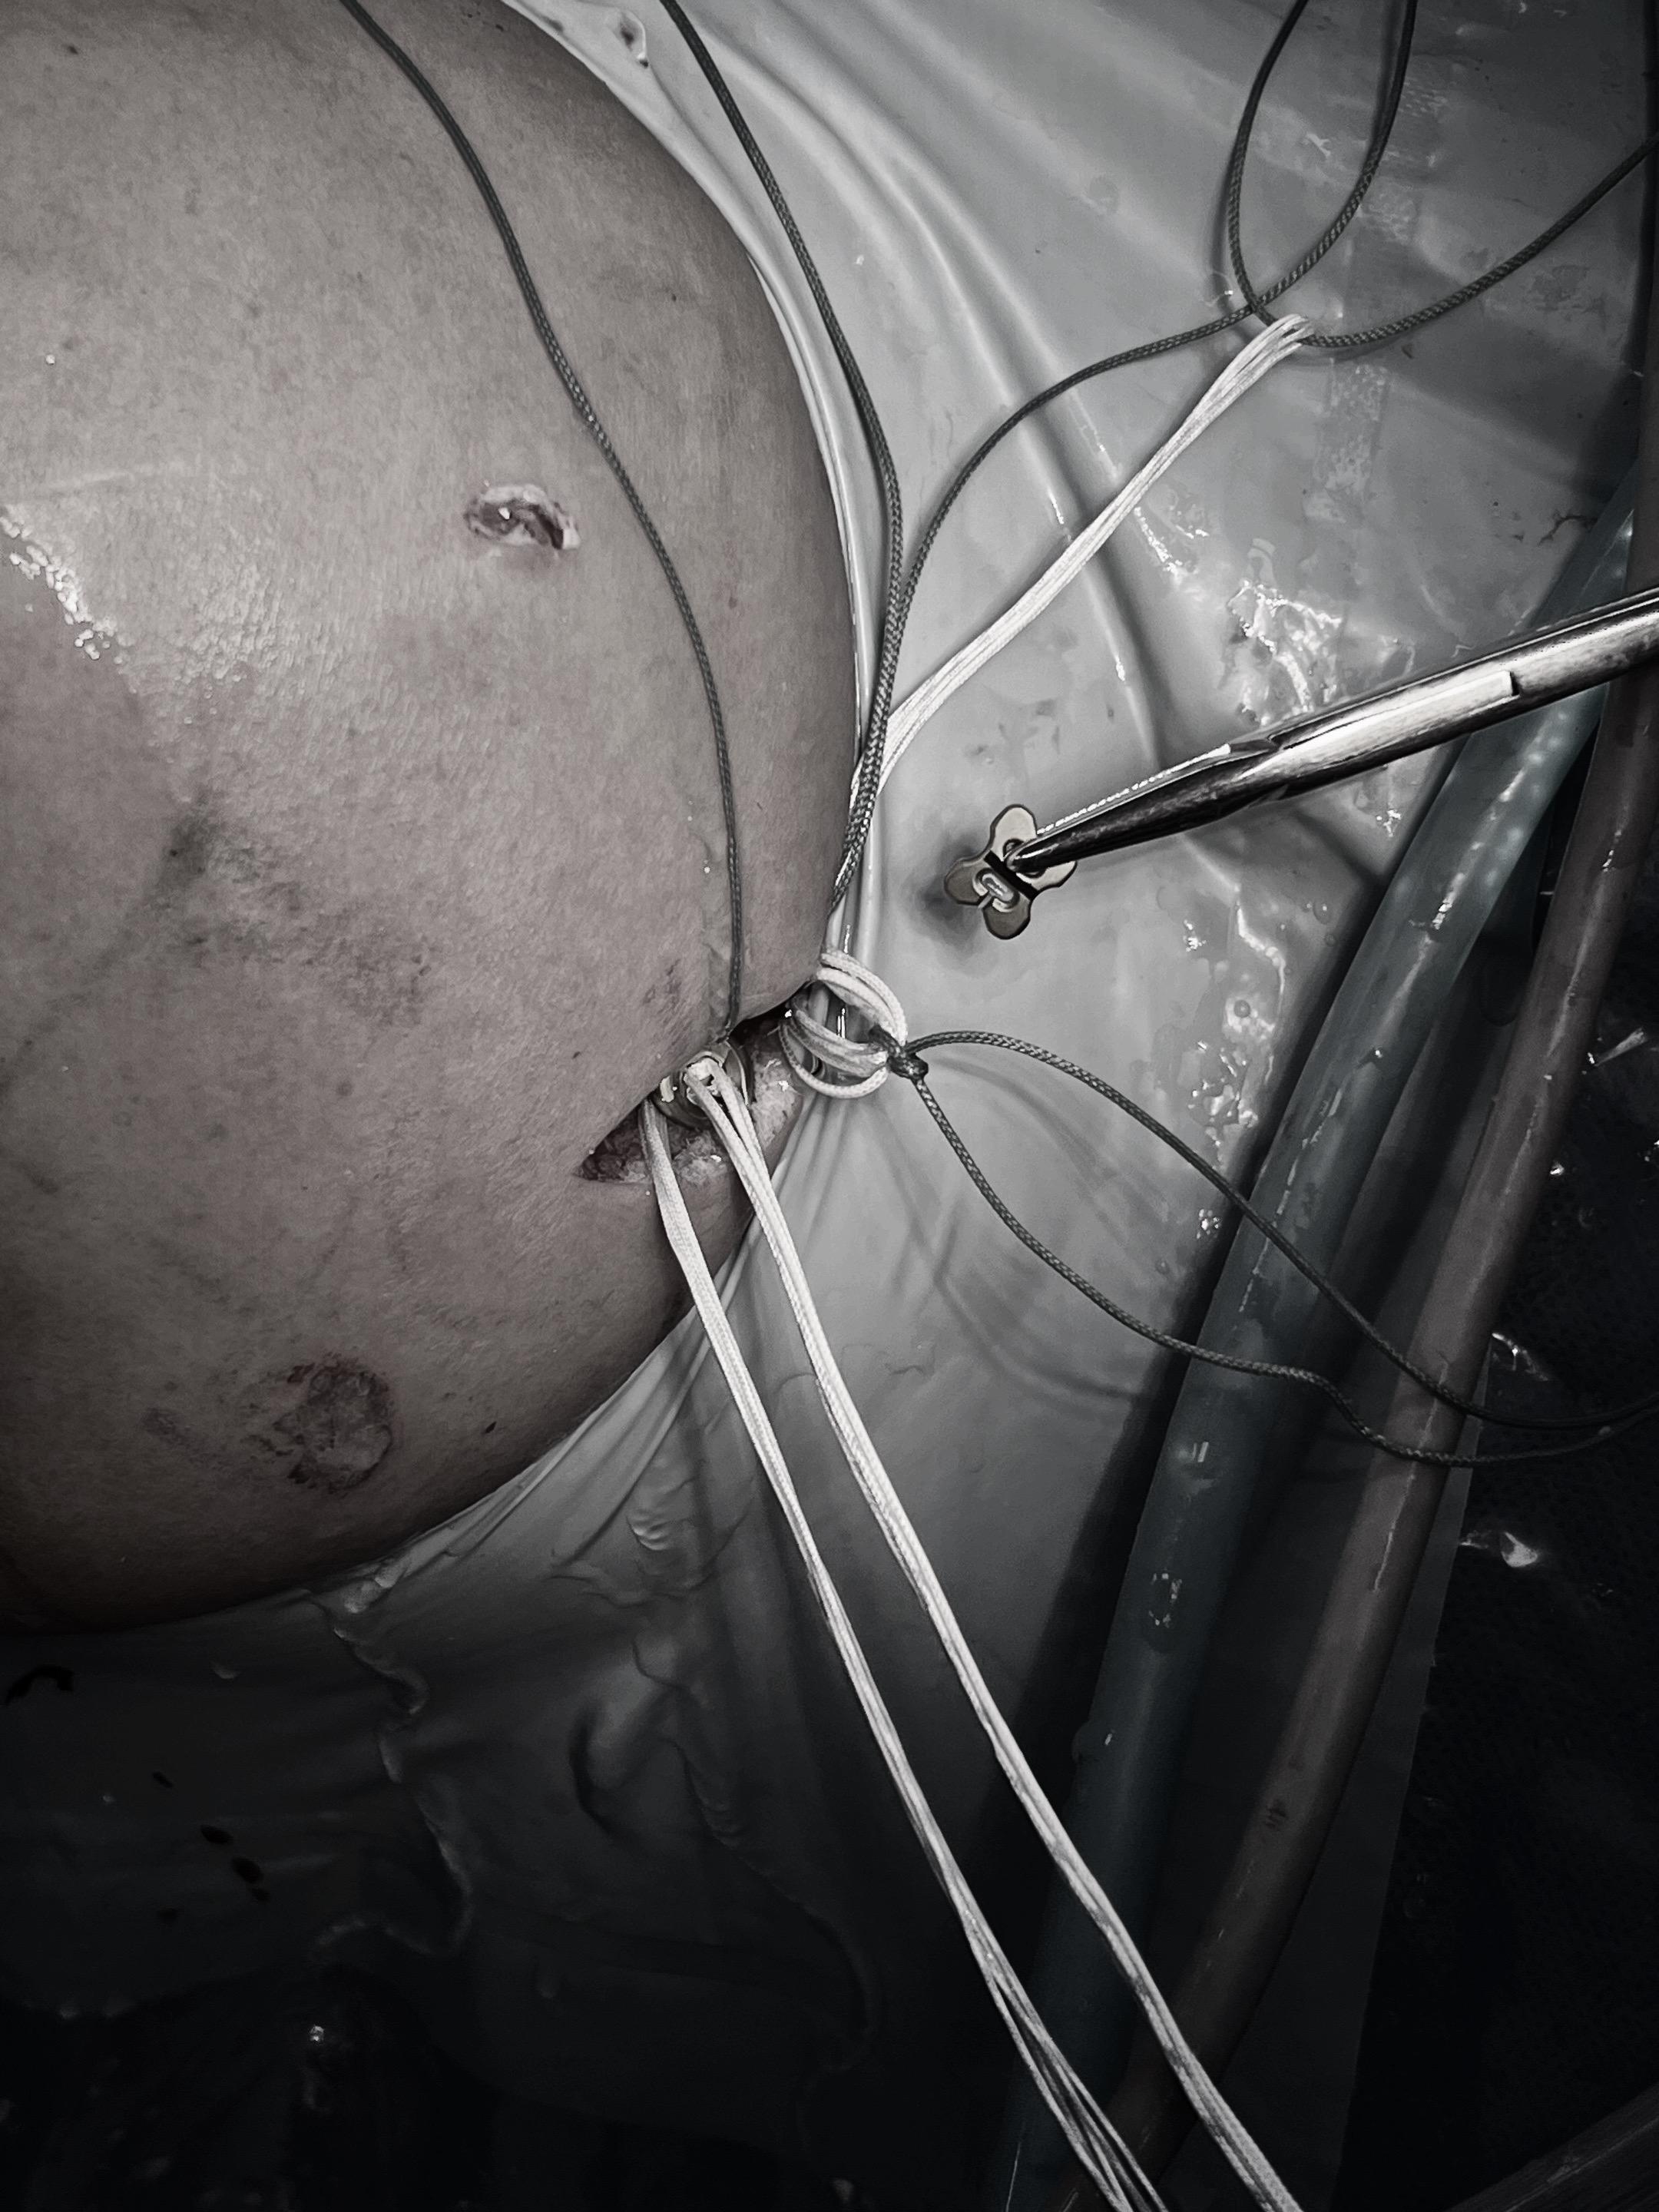

肩锁关节脱位。手术台上的每一次突破,都离不开前辈的倾囊相授。感谢赵立连主任的悉心指导,从理论到细节。